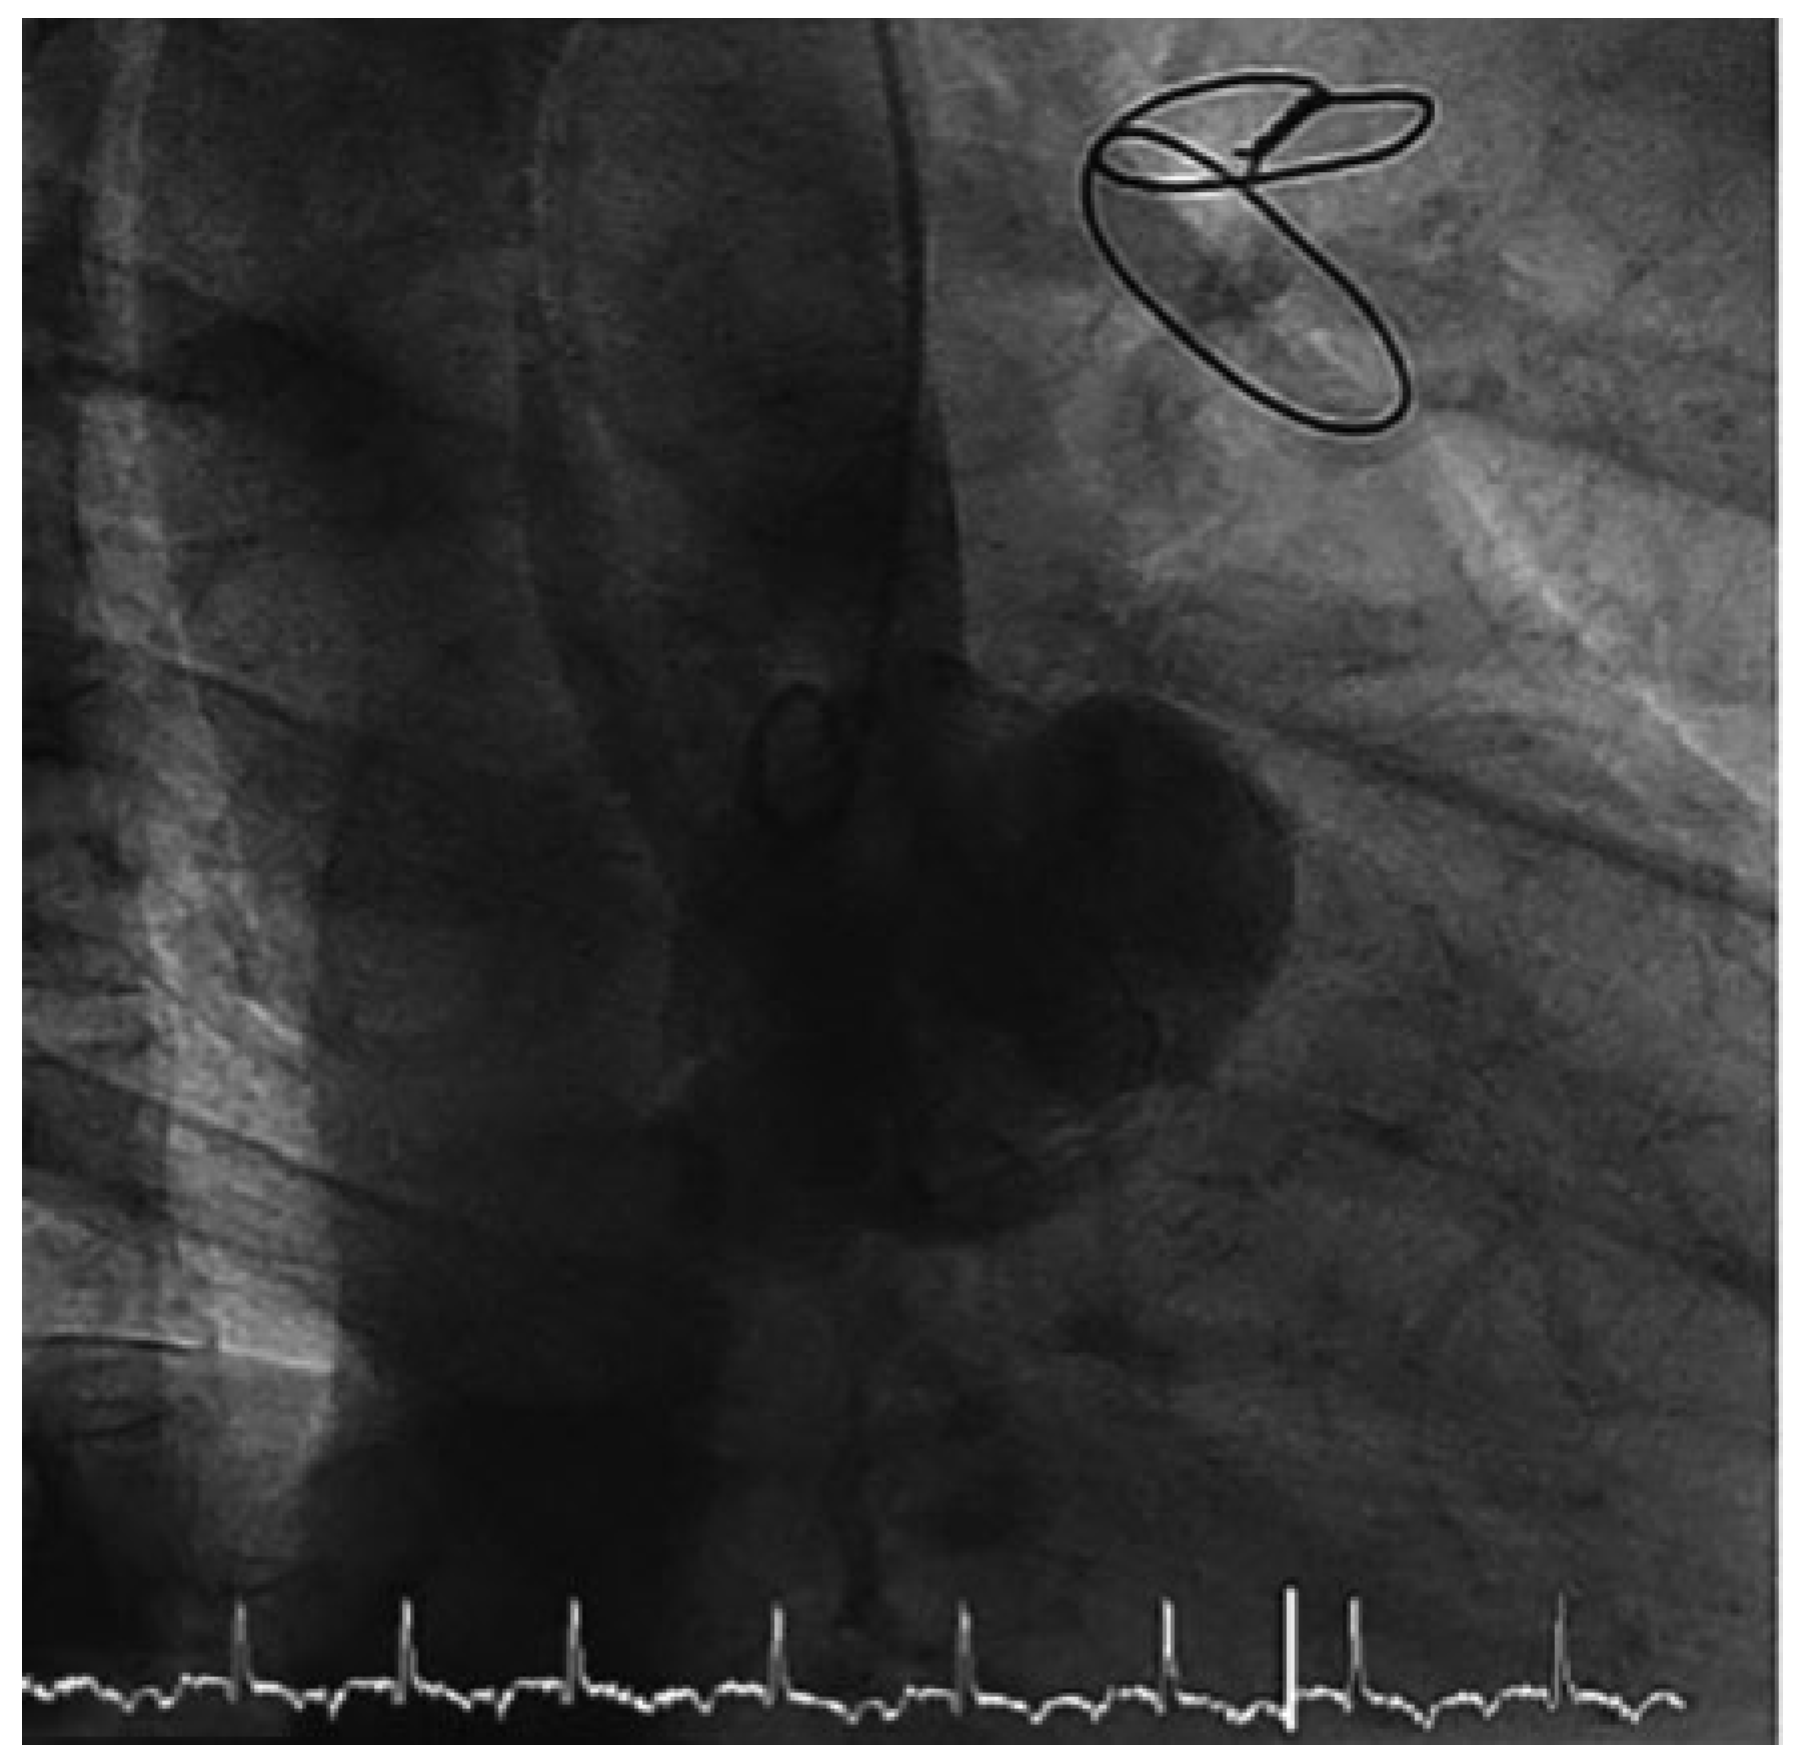

Intraoperative echocardiography showed a disconnection of the aortic valve prosthesis with a huge abscess surrounding the annular area (Figure 3a,b). For the first time, aortic insufficiency was diagnosed (Figure 3b). The biological aortic prosthesis could be removed without any difficulty only by elevation with forceps from the right coronary sinus, where the insufficiency was detected before. A large annular abscess had to be eradicated (Figure 4). Afterwards, a biological freestyle aortic root prosthesis (Freestyle, Medtronic) was implanted to avoid as much artificial material as possible. Additionally, epicardial pacemaker wires for the right atrium and right ventricle were implanted during the operation because of the high risk of atrioventricular block after eradication of the huge abscess.

Figure 4. Intraoperative view: The aortic prosthesis could be removed without any difficulty only by elevation with the forceps from the right coronary sinus, where the insufficiency was detected before.